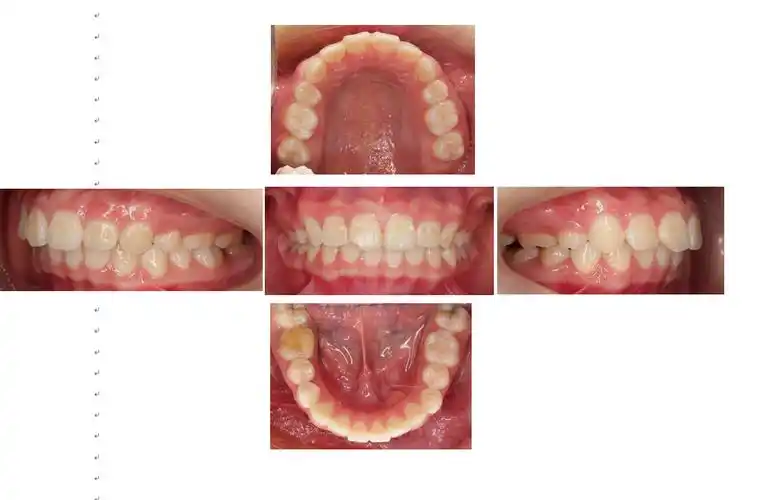

请问我这样的牙齿,需要拔掉第一双尖牙吗?

图片尺寸500x375